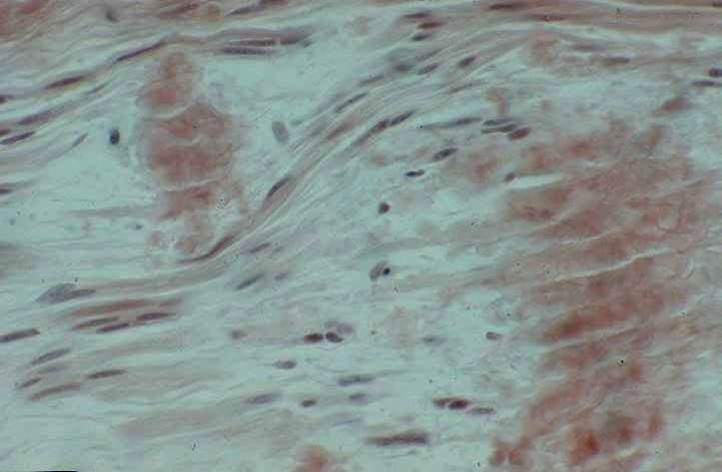

L’amylose héréditaire fait produire principalement par le foie une protéine modifiée (la transthyrétine). Cette protéine s’accumule majoritairement dans les nerfs périphériques et dans d’autres organes (cœur, œil, rein…) sous forme de dépôts fibrillaires (dits « amyloïdes »).